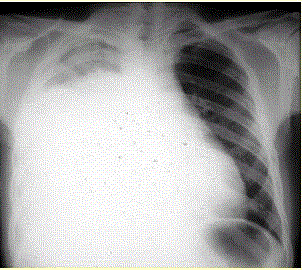

患者男,34岁。进行性胸闷、气促1个月余,伴有干咳、右胸隐痛以及消瘦,无咯血、发热、盗汗、潮热等。(提示 胸部X线检查如图所示。)诊断明确后可考虑...

问题 患者男,34岁。进行性胸闷、气促1个月余,伴有干咳、右胸隐痛以及消瘦,无咯血、发热、盗汗、潮热等。(提示 胸部X线检查如图所示。) 诊断明确后可考虑的治疗方法是(提示 患者经积极处理后上述症状明显好转。1周后已明确诊断。)

选项 A.外科手术 B.全身化疗 C.抗结核治疗 D.利尿治疗 E.化学性胸膜固定术 F.埋置胸腔导管引流 G.抗感染治疗

答案 BEF